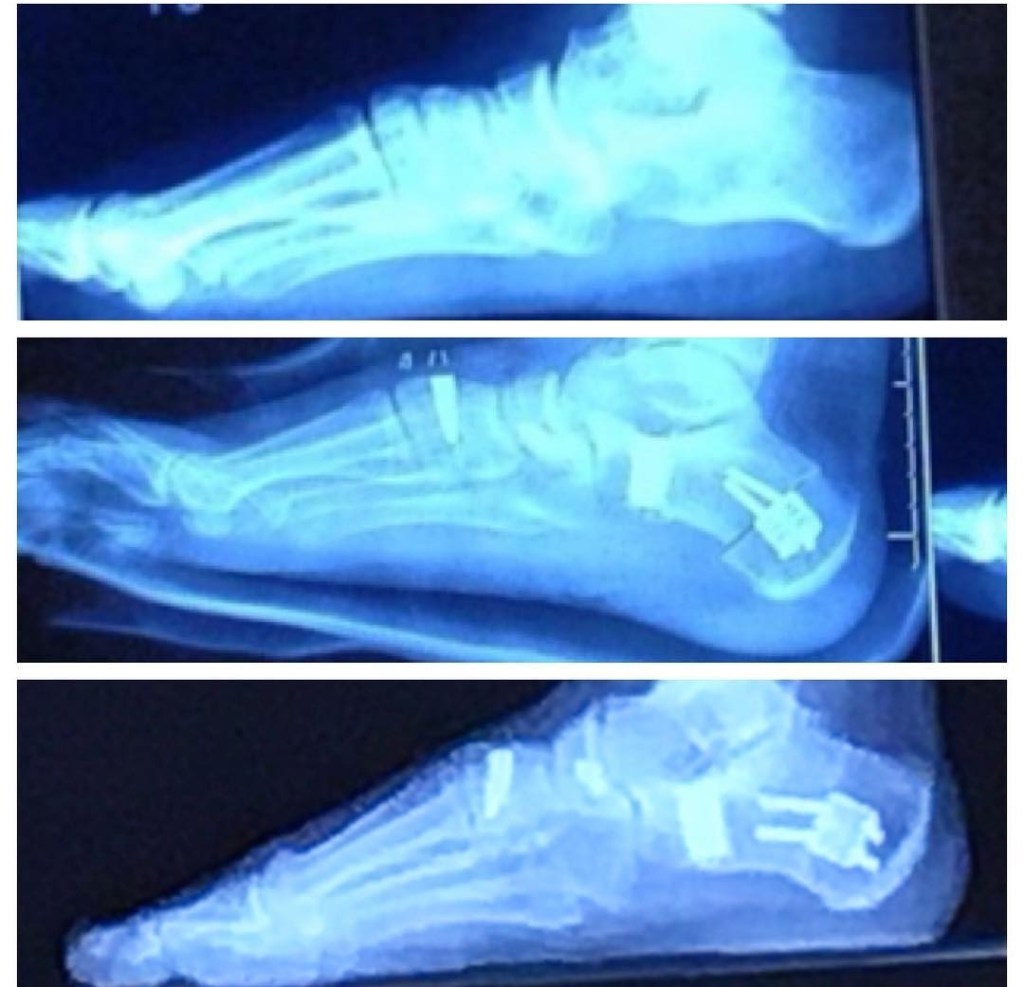

What they ended up having to do was two surgeries, about 6 months apart on each foot, and saw apart the bones, insert porous titanium wedges that the bones would grow into to form new arches, chop of a big chunk of stretched out tendon that had died and anchor the healthy bit down, and take a graft of muscle from my calf to attach to my Achilles to make it longer.

I had to spend months in physical therapy learning basic motions of walking, searing pain as nerves regrew, itchy casts, battling New England weather in crutches and mobility scooters, but in the end it was worth it. No pins and a permanent solution. I will not be running any marathons any time soon unless I do a whole lot more PT but now I have feet that will carry me anywhere I want in this earth.